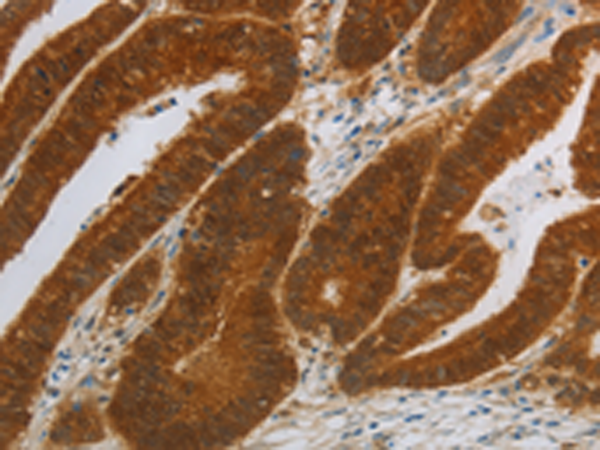

分类: 科研抗体货号: P11281别名: AKA; ngn1; Math4C; bHLHa6; NEUROD3应用: WB,IHC反应种属: Human